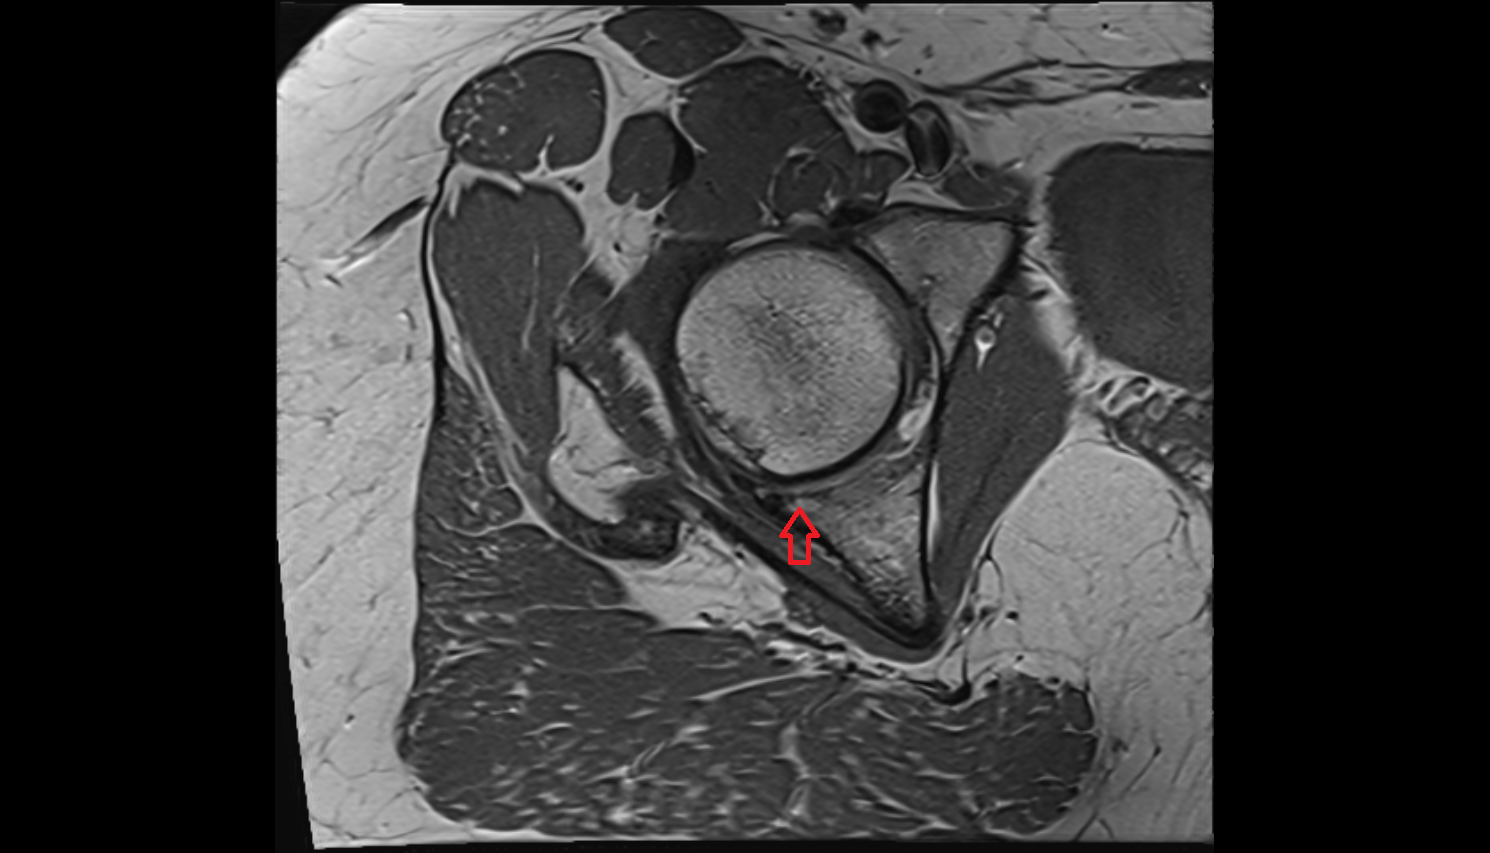

- Head of femur

- Acetabular labrum

- Hip joint